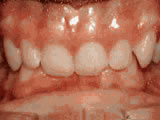

Missing lateral incisors

This patient’s lateral incisors were congenitally missing. She had braces for 20 months to move the teeth into their correct positions, then the missing teeth were replaced with bonded “Maryland” bridges